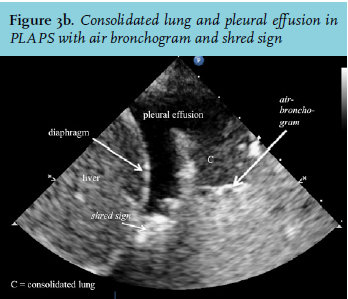

C-lines, air bronchogram, shred sign and pleural effusions

Alveolar consolidation causes typical ultrasound patterns at the different scanning points. At the anterior points, this yields C-lines, identified by a curvilinear aspect of the pleural line (figure 2e). This is caused by adjacent consolidated tissue.23 Pulmonary consolidations are fluid disorders. The non-aerated lung tissue is therefore easily traversed by ultrasound beams and creates an image comparable with that of liver tissue (figure 3a and b). Virtually all consolidations touch the pleural line. However, because of gravity, consolidation usually appears first at the PLAPS point.14 For similar reasons, pleural effusions also first appear at the PLAPS point (figure 3b). They can be hypoechoic or hyperechoic with particles. Hyperechoic effusions are associated with exsudate, but accuracy is not perfect.25 Hyperechoic effusions in combination with consolidated lung tissue at the PLAPS point are associated with the diagnosis of pneumonia. Consolidations can be further analysed by looking for air bronchograms or the shred sign (figure 3b). An air bronchogram is caused by reflection of ultrasound beams in the air-filled bronchi surrounded by consolidated tissue. The shred sign appears when the border of aerated lung and consolidated lung is not sharp. Both are suggestive of pneumonia. Furthermore LUS will identify the presence, size, and nature of an effusion and can be used to guide thoracocentesis (figure 3b).